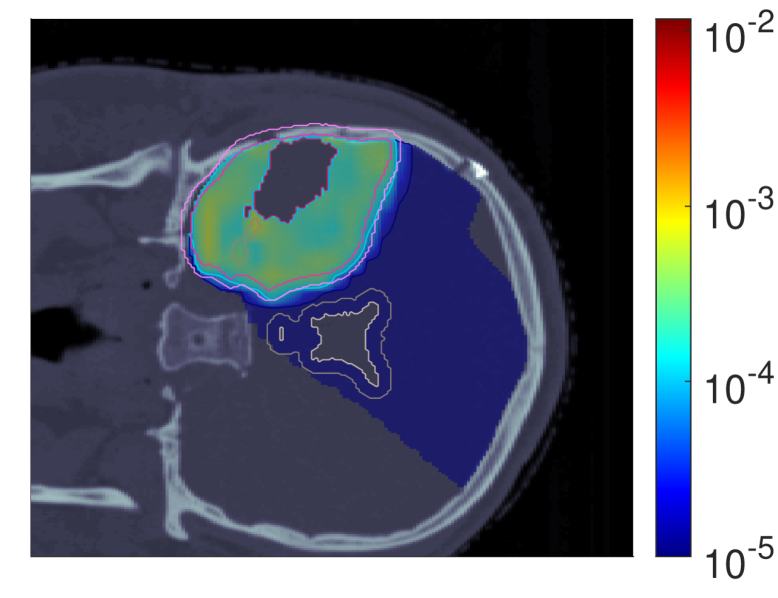

III.A.3 Probability of lesion origin pp

Figure 7 shows the POLO maps resulting from voxel-wise evaluation of the sigmoid-transformed linear predictor η\eta from Equation 1 with the input slice images for dRBE,fxd_{RBE,fx} and ldl_{d}.

NTCP30 %NTCP\approx{$30\text{\,}\mathrm{\char 37\relax}$} NTCP20 %NTCP\approx{$20\text{\,}\mathrm{\char 37\relax}$} NTCP10 %NTCP\approx{$10\text{\,}\mathrm{\char 37\relax}$}

pp (NTCPp)(NTCP_{p})

Refer to caption Refer to caption Refer to caption

pp (LSEp~)(LSE_{\tilde{p}})

pp (H~p)(\tilde{H}_{p})

pp (H~p~)(\tilde{H}_{\tilde{p}})

Figure 7: Optimal slice images of the probability of lesion origin pp for NTCPpNTCP_{p}, LSEp~LSE_{\tilde{p}}, H~p\tilde{H}_{p} and H~p~\tilde{H}_{\tilde{p}} at different NTCP levels. Considering the slice images for dRBE,fxd_{RBE,fx} and ldl_{d} from Figure 3 and Figure 5, the calculated pp values can be deduced from the prediction model. For example, hot spots are primarily found where high dRBE,fxd_{RBE,fx} values meet high ldl_{d} values, and for the voxels inside the 4 mm4\text{\,}\mathrm{mm} ventricular fringe where bb boosts the probability prediction. We take from these results that the POLO model-based optimization of the LGG sample patient’s proton plan achieves its goal, i.e., reducing pp in the region of interest.

For NTCPpNTCP_{p} and H~p\tilde{H}_{p}, we observed a (slight) reduction of dRBE,fxd_{RBE,fx} in the target volume and in the lower region overlapping with the VS, as well as a redistribution of ldl_{d} from the target volume to the margin of the PTV. Correspondingly, we see an overall reduction of pp in the target volume, together with an increasing attenuation of the hot spots around the marginal region of the PTV, and an elimination at the lower end of the VS. At strong down-regulation of the NTCP, the values are approximately one order of magnitude smaller, with peaks in the intersections to the 4 mm4\text{\,}\mathrm{mm} ventricular fringe and in regions where dRBE,fxd_{RBE,fx} and ldl_{d} intensify.

LSEp~LSE_{\tilde{p}} showed a decay of dRBE,fxd_{RBE,fx} inside but not outside the target volume, and almost constant values of ldl_{d}, and we recognize this pattern again in the pp distributions: hot spots are softened by the isolation of high-dose and high-LET regions, and the pp values in the target volume follow the negative trend for dRBE,fxd_{RBE,fx} at lower NTCP levels. Even the “dose gap” that occurs at an NTCP of 20 %20\text{\,}\mathrm{\char 37\relax} in the upper part of the target volume can be read from pp. Last, for H~p~\tilde{H}_{\tilde{p}} we can correlate the results for dRBE,fxd_{RBE,fx} and ldl_{d} again to understand pp. The higher ldl_{d} along the PTV margin is reflected by larger pp values and local hot spots, while the region around the GTV exhibits smaller pp values due to the reduction of dRBE,fxd_{RBE,fx}. At the lowest NTCP level, dRBE,fxd_{RBE,fx} contracts around the GTV, leaving only a slightly upward region at the left margin of the PTV which resembles the high-LET region, and hot spots where dRBE,fxd_{RBE,fx}, ldl_{d} and bb interact reinforcingly.